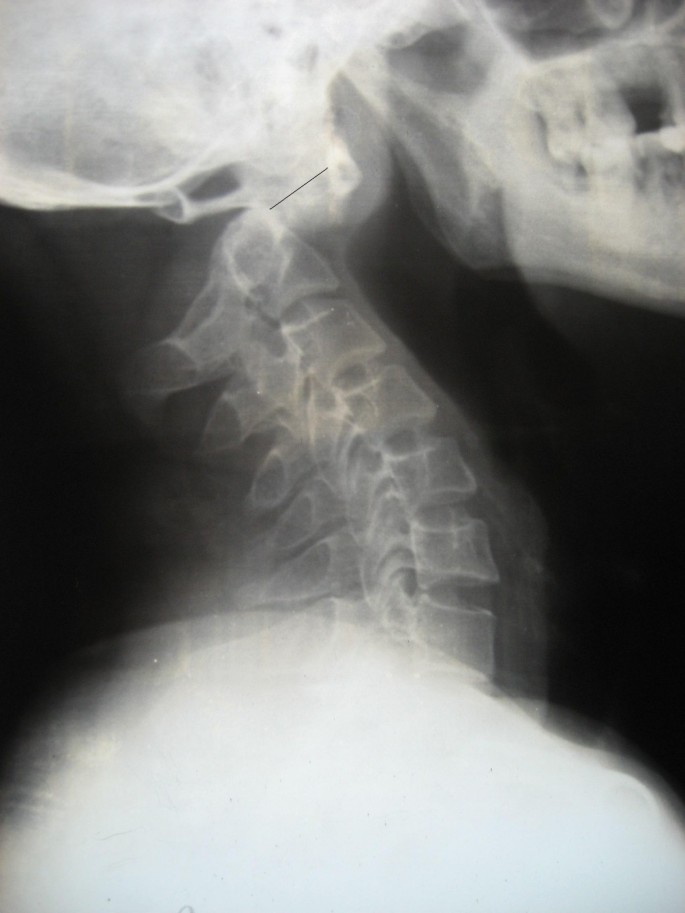

All subjects were assessed with plain anteroposterior, open mouth view and lateral flexion extension radiographs. Lateral radiographs help to verify that the C1-C2 complex has been reduced adequately before the surgery and to find the estimated length of the screws to be used (figure 2).